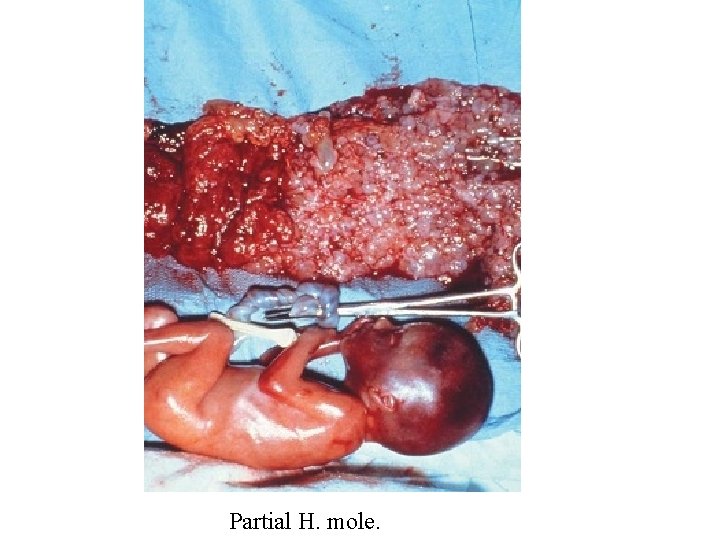

Partial H. Mole Microscopically: The enlarged, edematous villi and abnormal trophoblastic proliferation are slight and focal and did not involve the entire villi. There is a scalloping of chorionic villi Fetal or embryonic or fetal RBCs Macroscopically: The molar pattern did not involve the entire placenta. Uterine enlargement in excess of gestational age is uncommon. Theca-lutein cysts are rare Fetal or embryonic tissue or amnion

Partial Hydatidiform Mole Scalloping of chorionic villi Trophoblastic proliferation are slight and focal

Vesicles Maternal side Partial Hydatiform Mole

Fetal hand demonstrating syndactyly. The fetus had a triploid karyotype, and the chorionic tissues were a partial mole

Partial H. mole.